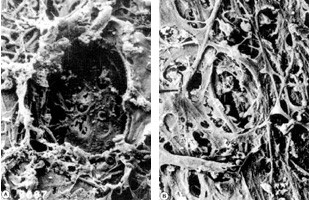

選択的レーザー線維柱帯形成術(SLT)より前のレーザー線維柱帯形成術では、レーザー光線の当たった部分の線維柱帯が壊れてしまうので、時間がたつと瘢痕(はんこん)になり、眼圧がまた上がってくるという欠点がありました(図3左)。

しかしSLTは、線維柱帯のフィルターの目につまった細胞のカスだけ(色素細胞)を選択的に蒸発させる(図4)ので、線維柱帯自身には傷害を与えず(図3右)、フィルターがまた目詰まりして眼圧が上がってきたら、繰り返し治療することができます。

図3 レーザー治療後の繊維柱帯の電子顕微鏡写真

(左:SLTより前のレーザー繊維柱帯形成術、右:SLT)